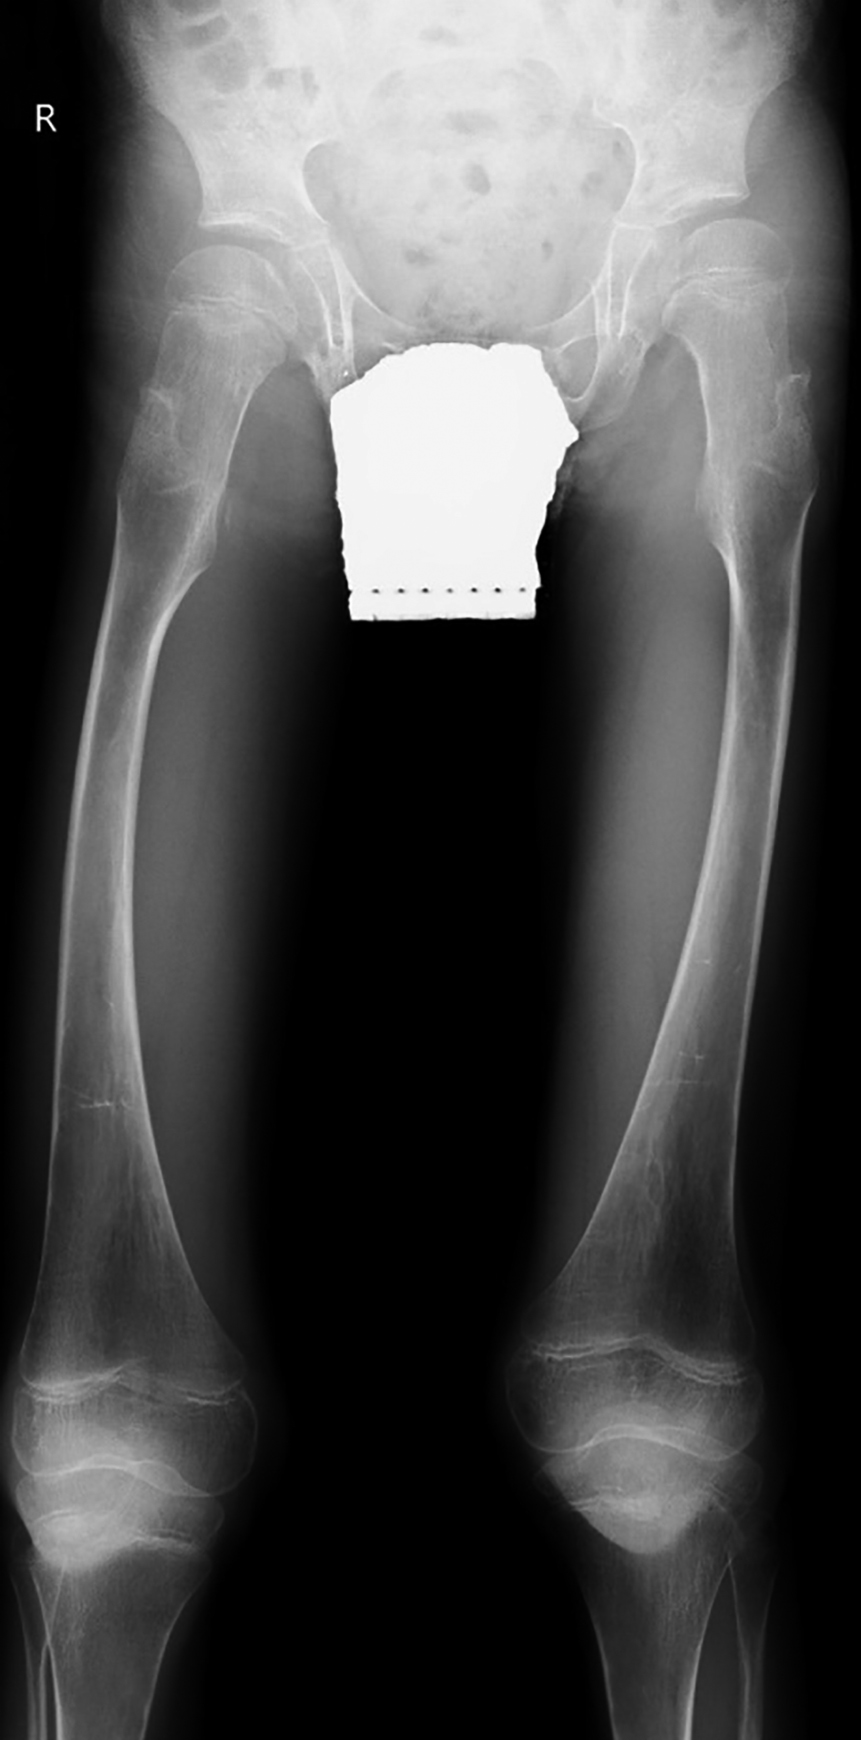

Рисунок 2. Пациент №2, 5 лет 6 мес., с синдромом Хатчинсона-Гилфорда.

Рентгенография таза с захватом нижних конечностей на протяжении. Выраженные изменения формы и структуры эпифизов и метафизов бедренных костей.

Первичное обследование было проведено в возрасте 5 лет 6 месяцев. Наблюдалась тяжелая задержка роста и дефицит массы тела, классические прогероидные черты лица (тонкая мраморная сухая гиперпигментированная кожа, выраженная венозная сеть на голове, нижних конечностях, выраженный периорбитальный цианоз, цианоз носогубного треугольника, треугольное лицо, клювовидный нос, микрогнатия, шарообразные глаза, экзофтальм, пушковый волос на голове, редкие брови, ресницы), генерализованная липодистрофия. При осмотре ортопеда отмечались выраженные контрактуры суставов кистей, в том числе пальцев; ограничение подвижности в лучезапястных суставах; разгибательные контрактуры в локтевых суставах; сгибательные контрактуры в коленных суставах; плоско-вальгусные стопы. По результатам обследования отмечалось незначительное отставание костного возраста, изменения формы и структуры эпифизов и метафизов бедренных костей (табл. 2, рис. 2).

Спустя 2 года, в 7 лет 5 месяцев, при осмотре наблюдалось прогрессирующее снижение росто-весовых показателей и деформации тазобедренных суставов, при этом фенотип пациента не изменился. Рентгенологически отмечено нарастание снижения плотности костной ткани метаэпифизарных отделов, преимущественно бедренных костей. С целью оценки минеральной плотности костной ткани была проведена денситометрия, по результатам которой был диагностирован остеопороз (табл. 2).